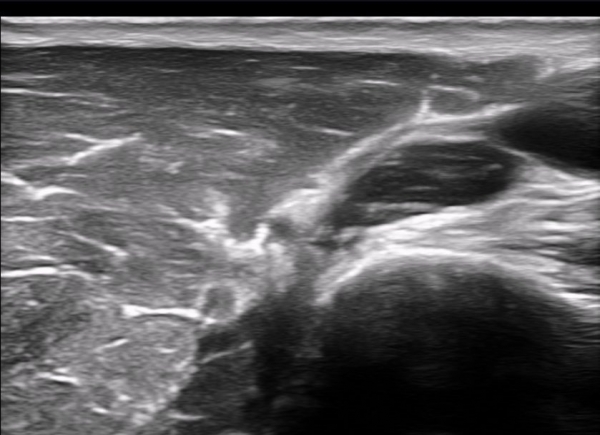

Å½ÃËÀÚ¸¦ Á¶±Ý ¸»´ÜÀ¸·Î À̵¿ÇÏ´Ï ±ÙÀ°ÇǺνŰæÀÇ À§ÃàÀÌ °üÂûµÇ°í(»çÁø 2) ŽÃËÀÚ¸¦ Á¶±Ý ´õ

¸»´ÜÀ¸·Î À̵¿ÇÏ´Ï ±ÙÀ°ÇǺνŰæÀÌ Á¤»êÀûÀ¸·Î °üÂûµÈ´Ù(»çÁø 3).

±ÙÀ°ÇǺνŰæÀÇ Á¾´Ü¸é°Ë»ç¿¡¼­ ±ÙÀ°ÇǺνŰæÀÇ ±¹¼ÒÀû ÇùÂø°ú ±ÙÀ§ºÎÀÇ Àú¿¡ÄÚ ºÎÁ¾ÀÌ °üÂûµÈ´Ù

(»çÁø 4, 5, 6,7) À̰ÍÀº ½Å°æÀÇ ¿°Àü(torsion)¿¡ ºÎÇÕÇÏ´Â ¼Ò°ßÀÌ´Ù.